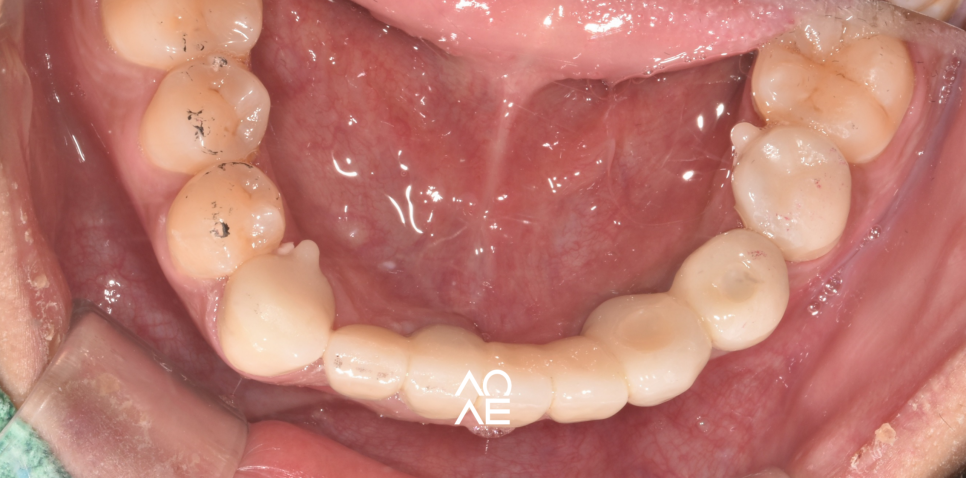

** 아래 저희 실제 환자분의 사진을 보더라도

잇몸뼈가 얇고 낮은게 보이시죠? **

사용된 사진은 동의하에 치료 과정의 이해를 돕기 위해서

사용합니다. 과정과 결과는 개인에 따라 다를 수 있어

의료진과의 충분한 상의가 필요합니다

| 치료 전 | 치료 후 |